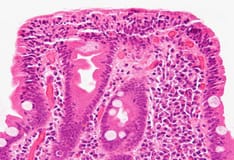

Papillary microabscesses form and progress to subepidermal vacuolization and vesicle formation in the lamina lucida, the weakest portion of the dermoepidermal junction (hematoxylin and eosin stain).